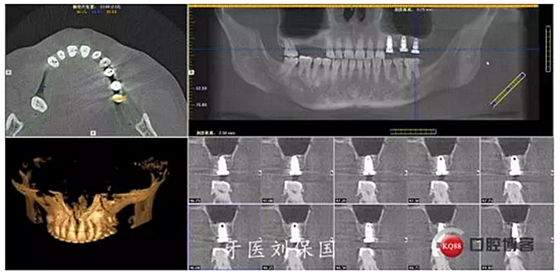

4.六個(gè)月后二期CT: